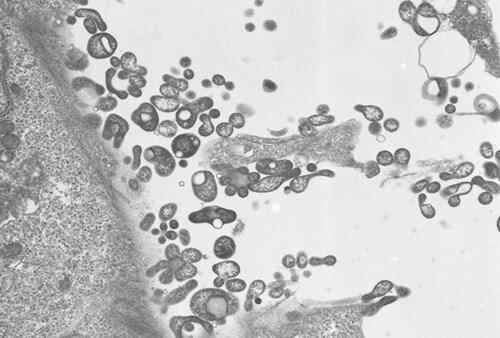

据俄罗斯塔斯社4日报道,世界卫生组织驻俄罗斯代表处负责人巴特尔·别尔德克雷切夫接受媒体采访时说,调查表明,俄罗斯境内没有出现“新病毒感染”,已知病例是由支原体感染引起了肺炎。

别尔德克雷切夫说,针对俄罗斯近来出现的咳血病例,世卫组织联系了俄罗斯相关机构。俄方按世卫组织要求提供了5例在莫斯科和莫斯科州登记的病例数据。经实验室研究确认,这5例病例所患疾病是支原体感染引起的肺炎,不是新病毒感染。

据俄罗斯塔斯社4日报道,世界卫生组织驻俄罗斯代表处负责人巴特尔·别尔德克雷切夫接受媒体采访时说,调查表明,俄罗斯境内没有出现“新病毒感染”,已知病例是由支原体感染引起了肺炎。

别尔德克雷切夫说,针对俄罗斯近来出现的咳血病例,世卫组织联系了俄罗斯相关机构。俄方按世卫组织要求提供了5例在莫斯科和莫斯科州登记的病例数据。经实验室研究确认,这5例病例所患疾病是支原体感染引起的肺炎,不是新病毒感染。